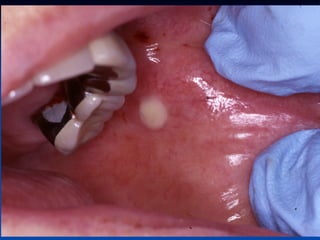

Mucocele

Ranula

n

Is a term used for

mucoceles that occur in

the floor of the mouth.

The name is derived

form the word rana,

because the swelling

may resemble the

translucent underbelly

of the frog.